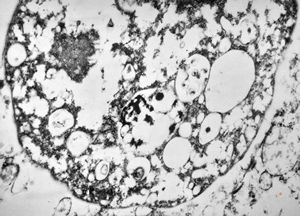

cytomegalovirus - pneumonia